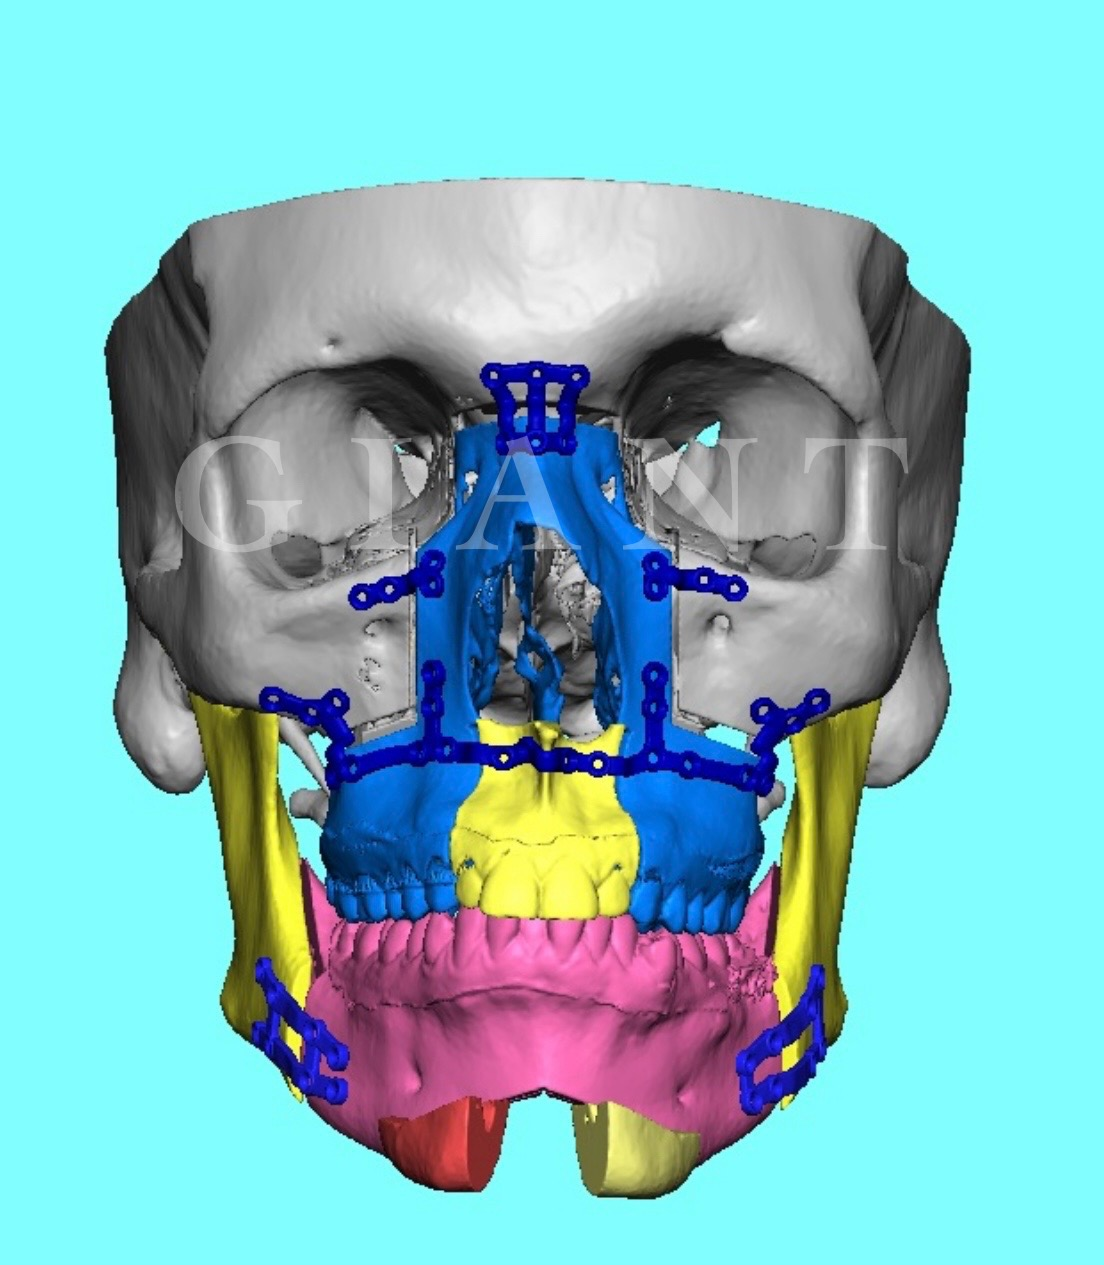

I just dont see any reason to bonesmash when we can do thisIts backed up by Science and I've seen hundreds of transformations on Discord

I have $7.56 in my Bank account bro.I just dont see any reason to bonesmash when we can do this

View attachment 4210290View attachment 4210293